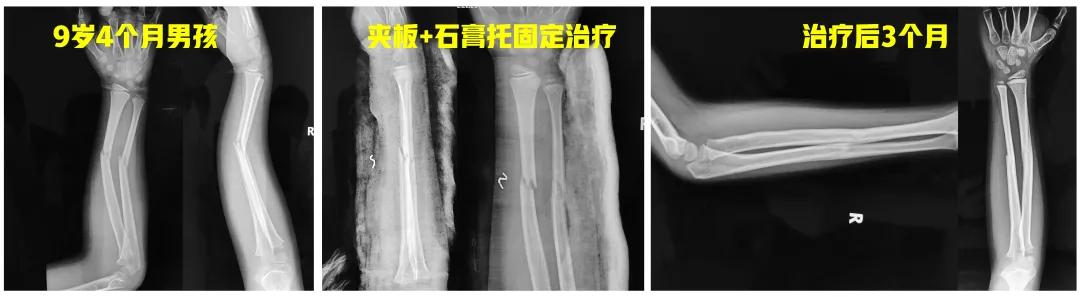

老师: 下面两个病例,分别是9岁4个月男孩的前臂中段骨折,保守治疗后3个月骨折对位、愈合良好。另外一个12岁男孩,早期外院保守治疗,三周时骨折再移位,于我院再次整复后恢复满意。